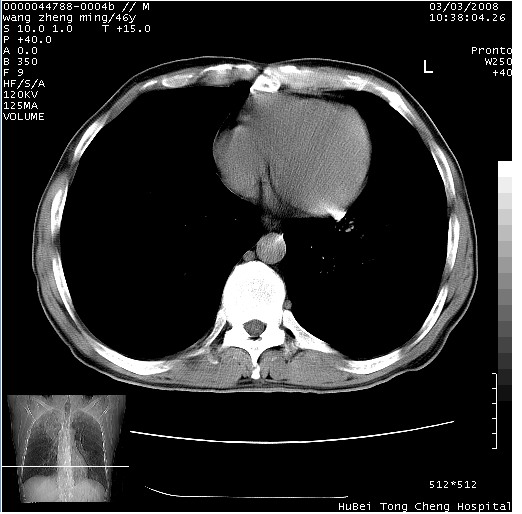

以下是引用卜一在2008-3-22 1:37:00的发言:[br]右肺实质性肿块,边缘不整,明显见毛刺征 分叶征及胸膜凹陷征,右上叶支气管明显变窄,远端散在的片状 斑片状实变影。另:左肺门较大肿块,支气管受累 变窄,远侧见阻塞性肺炎。纵隔内见肿大淋巴结。多考虑:右肺周围性肺癌伴左肺门 纵隔淋巴结转移!